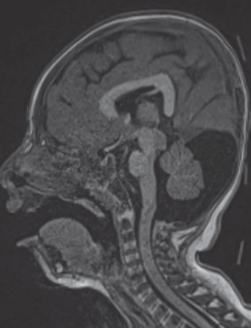

La resonancia magnética de cráneo identificó engrosamiento generalizado de la corteza cerebral de 16 mm, apariencia lisa macroscópica, poca profundidad de las cisuras de Silvio y disminución generalizada de la surcación. Se identificaron focos heterotópicos periventriculares frontales (figura 1). En el cuerpo calloso se observó la formación de un ángulo recto entre el cuerpo y el esplenio, así como la presencia de megacisterna magna (figura 2).

Figura 1 Resonancia magnética cerebral en secuencia T1 en corte sagital que identifica apariencia lisa y disminución de la surcación de la superficie cortical cerebral, así como heterotopías periventriculares frontales